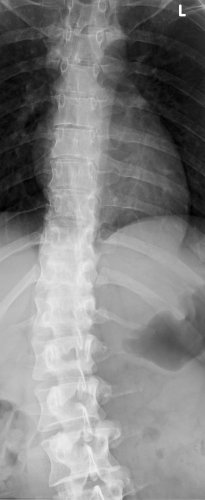

Ich habe eine festgestellte Skoliose, und weiß nun nicht wie es weiter geht, die Diagnose bekam ich bereits mit 14 oder 15 glaube ich,es kam auch zu einem Korsett damals, man wurde in der Schule viel gemobbt deswegen und ich habe die Sache auch damals überhaupt nicht ernst genommen,ich sah auch noch relativ normal am Rücken aus. Jedenfalls flog das Korsett schnell in die Ecke

Jetzt 9 Jahre älter und um einiges gescheiter halte ich es nicht mehr aus, ich sehe furchtbar aus denn in den Jahren hat sich ein richtiger Buckel auf der rechten Seite gebildet, Schmerzen haben mich immer begleitet aber ich hab das nicht so ernst gesehen,gesehen haben meinen Buckel sicher auch schon genug aber ich habe immer versucht das irgendwie durch die Kleidung zu verstecken,es ist so deprimierend wenn man sich nicht kleiden kann wie andere in meinem Alter

Jetzt so seit 2 Wochen habe ich tierische Schmerzen vom Ncken und den kompletten Rücken runter,ich bin also doch zum Arzt gegangen, da wurde dann alles komplett vom Rücken geröngt,die Bilder hab ich aber noch nicht gesehen. Beim Arzt war ich nur ganz kurz drin, er meinte nur es ist schlimm aber nicht zu spät. Hat mir jetzt Physio - und Ergotherapie verschrieben mit Massage und Reizstrom. Das beginnt nun alles nächste Woche.